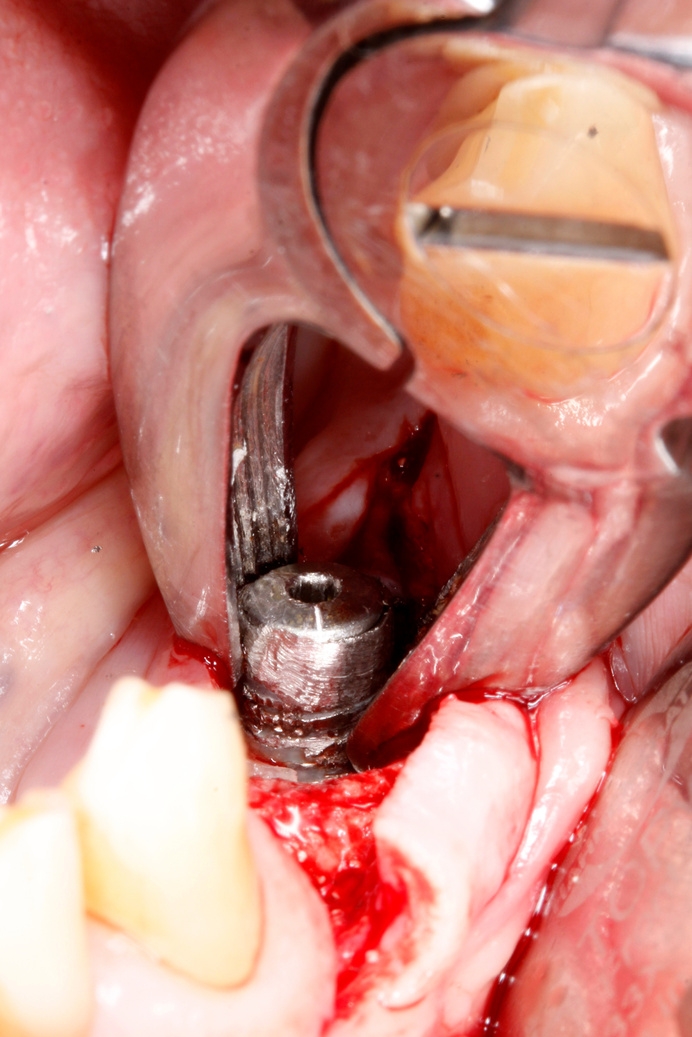

Fig 4: Surgical removal of the failed implant

After 2 months of non-surgical treatment and monitoring, the infection showed improvement but did not fully resolve.

A decision was made to surgically remove the failed implant ( Figure 5) and debride the infected area. The patient initially considered whether to replace the missing teeth with implants.

Following 3 months of healing, the patient opted for implant replacement. Two new implants were placed at sites 34 and 36, avoiding the bony defect from the previously removed 35. Guided bone regeneration was performed to address bone deficiencies and ensure long-term stability.